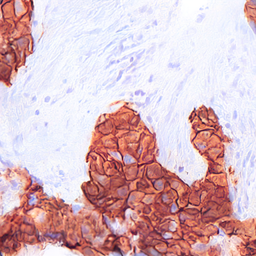

Refer to captionRefer to captionRefer to captionRefer to captionRefer to captionRefer to captionRefer to captionRefer to captionRefer to captionRefer to captionRefer to captionRefer to captionRefer to captionRefer to captionRefer to captionRefer to captionRefer to captionRefer to captionRefer to captionRefer to captionRefer to captionRefer to captionRefer to captionRefer to captionRefer to captionRefer to captionRefer to captionRefer to captionRefer to captionRefer to captionRefer to captionRefer to captionRefer to captionRefer to captionRefer to captionRefer to captionRefer to captionRefer to captionRefer to captionRefer to captionRefer to captionRefer to captionRefer to captionRefer to captionRefer to captionRefer to captionRefer to captionRefer to captionRefer to captionRefer to captionRefer to captionStyle Transfer [6]Ours (Nearby Style Cond.)Ours (Multi-Patch Style Cond.)StylesStylesStyles (selection, 3 of 10)LayoutsLayoutsLayouts

Figure 4: Image generation results with the HER2 dataset, for the style transfer baseline [6] (left), our proposed method trained with nearby patches as style source (center) and our proposed method trained with multi-patches as style source (right). Note that white represents tumor tissue in the layout images, while black includes all background structures.

Figures 4 and 5 show examples of generated images for the HER2 and CATCH dataset. The style transfer baseline [6] captures some of the staining characteristics for the HER2 dataset, but also creates some darker blurred areas, which are not commonly seen in HER2 images. On the CATCH dataset, the global color scheme is transferred to the synthetic images, but no delineation between tumor and background area is visible. For our method the generated images adhere to the spatial layout and also represent the styles in the query images for both the nearby and multi-patch configuration, even though the query images were not seen during training.